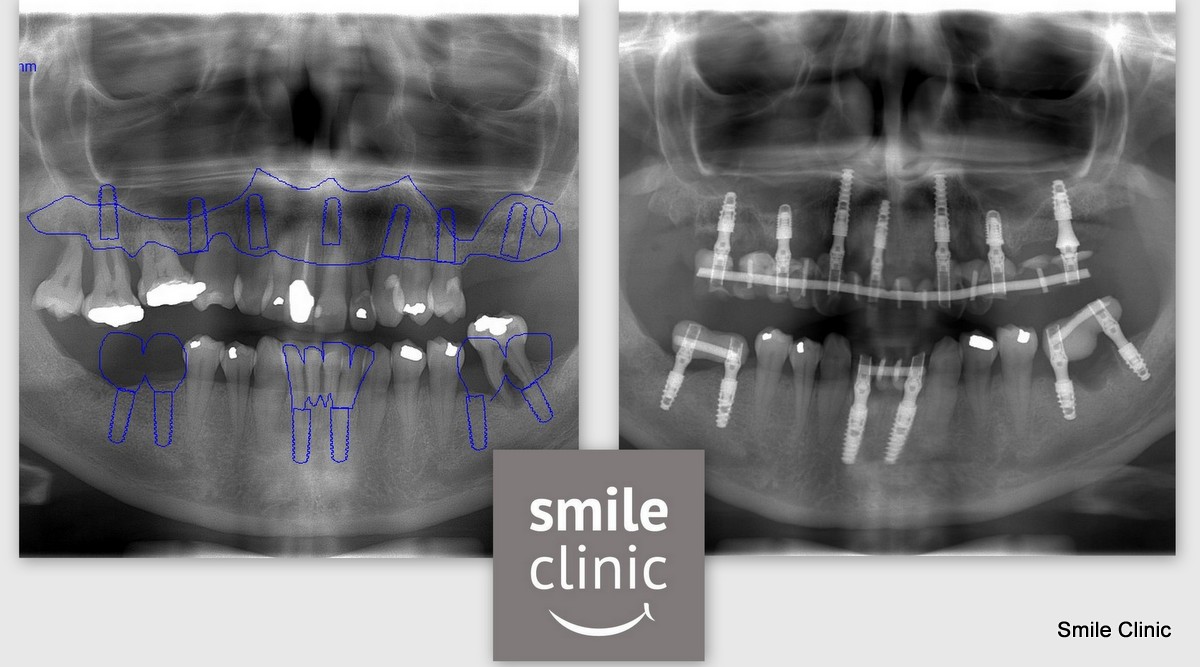

Jane came out to us first from Manchester for a free consultation & X-rays with Dr. Marek before returning at a later date to complete her dental treatment which, as you can see from the X-rays, included 13 dental implants & crowns.